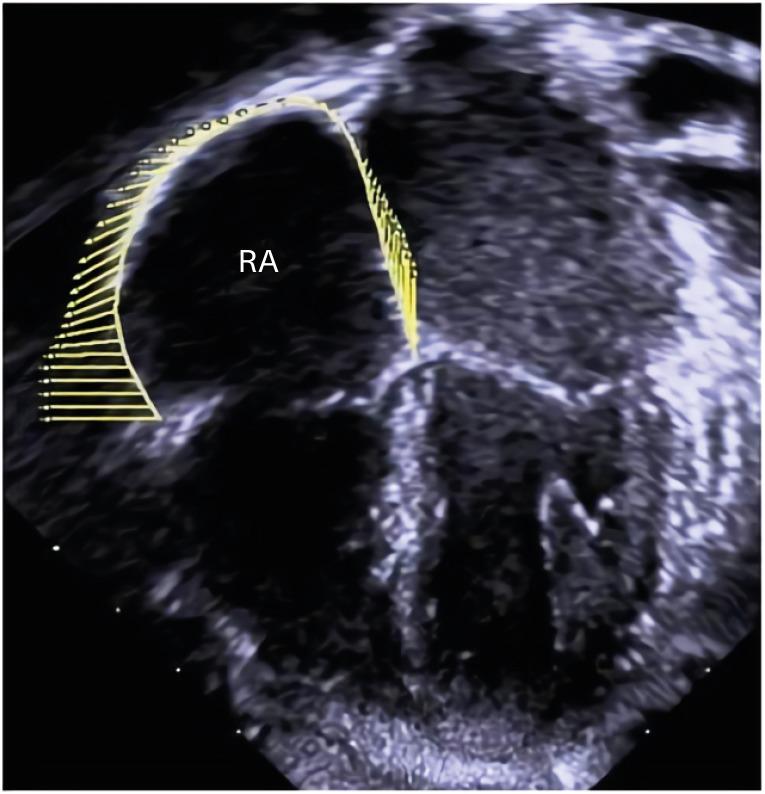

腺样体扁桃体肥大患儿的右心房变形力学

Right Atrial Deformation Mechanics in Children with Adenotonsillar Hypertrophy.

BACKGROUND

Children with significant adenotonsillar hypertrophy (ATH) may show right ventricular (RV) dysfunction. We aimed to evaluate RV dysfunction in such children before adenotonsillectomy by evaluating peak longitudinal right atrial (RA) strain (PLRAS) in systole. PLRAS, electrocardiogram (ECG) and conventional echocardiographic parameters were compared to distinguish children with significant ATH with sleep-related breathing disorder (ATH-SRBD) from controls.

METHODS

Fifty-six children (23 controls and 33 children with ATH-SRBD without symptoms of heart failure) were retrospectively studied. Preoperative echocardiograms and ECGs of children with ATH-SRBD who underwent adenotonsillectomy were compared to those of controls. Available postoperative ECGs and echocardiograms were also analyzed.

RESULTS

Preoperatively, prolonged maximum P-wave duration (Pmax) and P-wave dispersion (PWD), decreased PLRAS, and increased tricuspid annulus E/E' were found in children with ATH-SRBD compared to those of controls. From the receiver operating characteristic curves, PLRAS was not inferior compared to tricuspid annulus E/E', Pmax, and PWD in differentiating children with ATH-SRBD from controls; however, the discriminative abilities of all four parameters were poor. In children who underwent adenotonsillectomy, echocardiograms 1.2 ± 0.4 years after adenotonsillectomy showed no difference in postoperative PLRAS and tricuspid annulus E/E' when compared with those of the preoperative period.

CONCLUSIONS

Impaired RA deformation was reflected as decreased PLRAS in children with ATH-SRBD before adenotonsillectomy. Decreased PLRAS in these children may indicate subtle RV dysfunction and increased proarrhythmic risk. However, usefulness of PLRAS as an individual parameter in differentiating preoperative children with ATH-SRBD from controls was limited, similar to those of tricuspid annulus E/E', Pmax, and PWD.